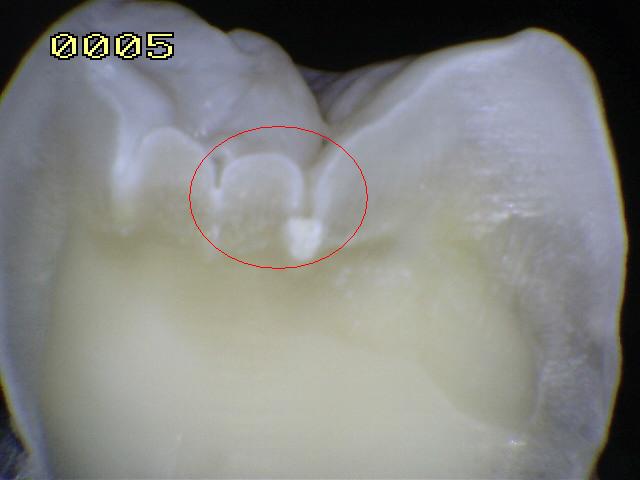

Código 1: Primer cambio

visible en el esmalte seco

- Cuando se ve húmeda no hay evidencia de

cambio en el color atribuibles a la actividad de caries, pero después

del secado con aire por 5 segundos, una opacidad de caries o cambio de

color (mancha blanca o lesión marrón) es visible, lo cual no es consistente con

la apariencia clínica del esmalte sano, el cambio de color se

limita al fondo de la fosa o fisura. La aparición de estas áreas

de caries no es consistente con la de las fosas y fisuras teñidas como

se define en el código 0.